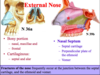

Label this